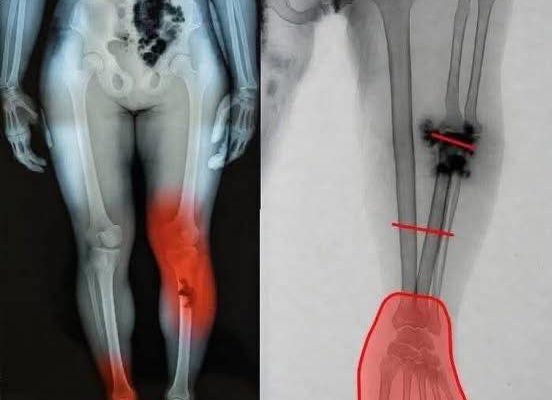

A recurring example involves dramatic posts claiming that people who received a COVID-19 vaccine may be at risk of severe illness. These posts often feature emotionally charged images, such as medical illustrations suggesting a syringe being injected directly into the heart. Accompanied by vague warnings like “If you got the COVID vaccine, you should know this,” such content spreads quickly and captures attention.

Fear-based health messaging is especially effective in this environment. Images that imply immediate danger—such as a syringe pointed at a heart—activate a natural instinct to protect oneself. Before viewers even read the accompanying text, the visual message has already created a sense of urgency.

For instance, some posts mention the condition known as myocarditis—a form of heart inflammation. When this medical term appears alongside dramatic images or warnings, it can give the impression of widespread risk. However, without details about frequency, severity, or comparison to other risks, the information becomes distorted.

One of the most discussed conditions is myocarditis. This involves inflammation of the heart muscle and was observed in a limited number of cases after certain mRNA vaccines, particularly among adolescent and young adult males.